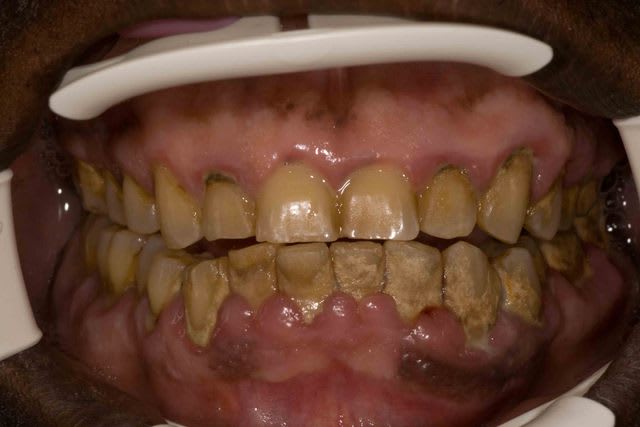

levm

Bande de petits joueurs

dentiste57

eh ben voilà! ça y est j'ai vomi...

Céramik

Vu cette semaine, en 2 jours,

3 cas d'allergie à la brosse à dents...